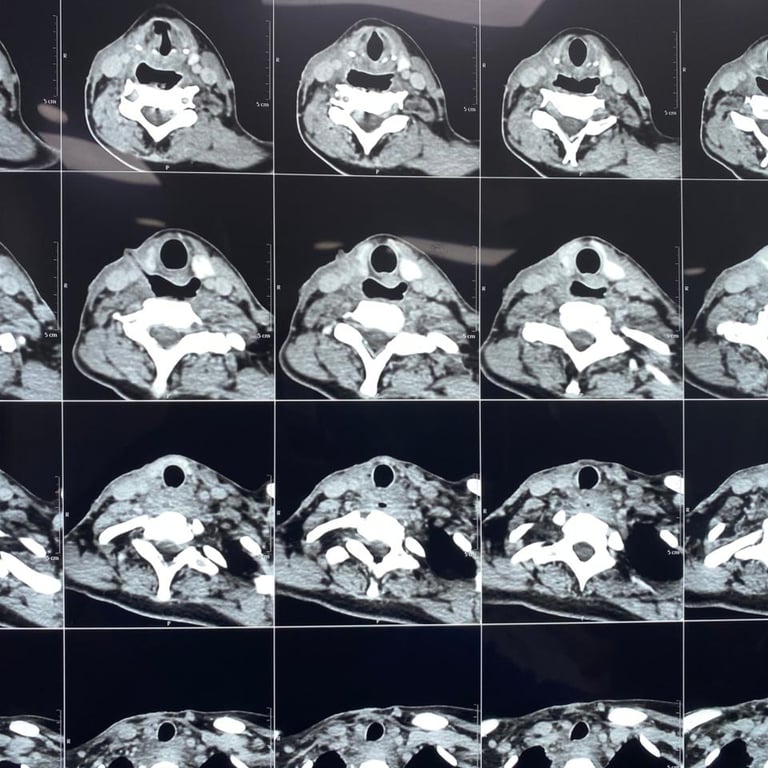

Upon presentation to me, a thorough clinical evaluation was performed, including endoscopic examination and imaging with CT and MRI.

In addition to confirming the chronic pharyngocutaneous fistula, imaging revealed a previously undetected large pharyngeal pouch, contributing to persistent leakage and impaired swallowing. Identifying this concealed pathology was critical to designing a definitive surgical strategy.